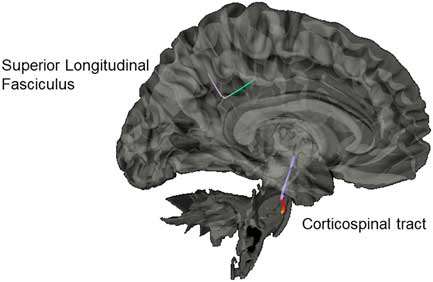

Diffusion Group Connectometry Results

Results from the connectometry analyses revealed significant differences in isotropic diffusion between the control and SRC groups at time 1, with the SRC group showing increased isotropic value of the diffusion orientation density function along a segment of the CST (FDR=0.20) and the SLF (FDR=0.27; Figure 4). No significant correlations were found between neurocognitive performance on the ImPACT or TSS and diffusion metrics. No significant differences were seen between the control group and the SRC group at time 2.

Fig. 4 Significant difference in isotropic diffusion between the control group and SRC group at time 1, with the SRC group showing greater diffusivity in the corticospinal tract and the superior longitudinal fasciculus compared to the control group.

Our group connectometry analysis revealed disrupted diffusion within the CST and the SLF at time 1 in the SRC group compared to the control group. The CST and SLF have been consistently found to be altered in mTBI, and negatively correlated with clinical measures of severity of injury (e.g., Glasgow Coma Scale; Gardner et al., Reference Gardner, Kay-Lambkin, Stanwell, Donnelly, Williams, Hiles and Jones2012). Disruption of diffusion of the CST acutely post-SRC is hypothesized to be due to compressed intracellular space along the CST due to local inflammation and cytotoxicity (Henry et al., Reference Henry, Tremblay, Tremblay, Lee, Brun, Lepore and Lassonde2011; Virji-Babul et al., Reference Virji-Babul, Borich, Makan, Moore, Frew, Emery and Boyd2013).

With regard to the SLF, our results indicate the utility of the GQI approach to being more sensitive to dense white matter areas with crossing fibers, as our results indicated differences in a directional change of the SLF. This identified segment is part of the posterior portion of the SLF as it bends inferiorly from frontal lobe projections toward the tempo-parietal junction, and then branches to project toward the IPL, specifically the supramarginal gyrus. This is a centrally localized junction of several other white-matter tracks as well, including the arcuate fasciculus and posterior cingulum. This area has been reported in other studies to be particularly vulnerable to the linear (i.e., coup- contrecoup) injury and rotational forces that can damage the integrity of the crossing fibers in this dense area (Cubon, Putukian, Boyer, & Dettwiler, Reference Cubon, Putukian, Boyer and Dettwiler2011; Churchill, Caverzasi, Graham, Hutchison, & Schweizer, Reference Churchill, Caverzasi, Graham, Hutchison and Schweizer2017).

Overall our diffusion results are in line with our rs-fMRI results, which found specific positive correlations between cognitive performance and rs-fMRI within the IPL (including supramarginal gyrus) at time 1 and time 2. It is likely that activity in the IPL, in addition to negative modulation of frontal regions (SFG, MFG), may reflect disruption of white matter tracks between these regions known to be vulnerable to injury.